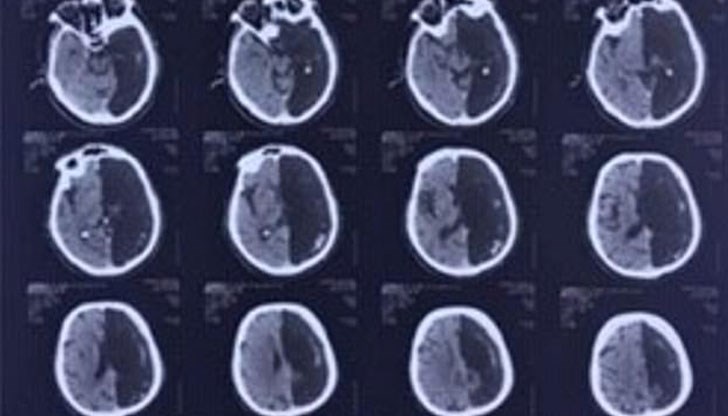

Медиците в Москва откриват този разтърсващ факт по време на компютърна томография на мозъка, след като пациентът е приет в болница след микроинсулт, пише "Дейли мейл", предава 24 часа.

"Рентгенолозите правят компютърна томография на главата му и са озадачени - частта от мозъка на пенсионера, където се предполага, че исхемичната атака се е случила, изобщо не съществува. Вместо лявата част от мозъка на компютърната графика се вижда черно петно - кухина", казва още тя.